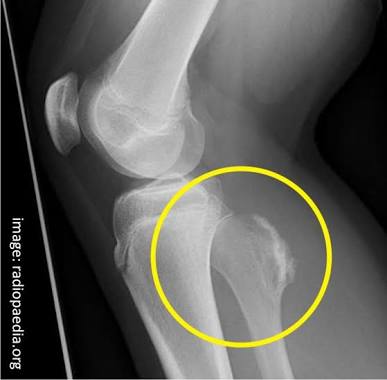

Reason for Splinting

- To limit the motion of bone fragments, bkne ends, or dislocated joints.

- To lessen the damage to muscle, nerves, or blood vessels caused by broken bones.

- To help prevent a closed injury from becoming an open injury.

- To lesse the restriction of blood flows caused by bone ends or dislocation .compressing blood vessels.

- To reduce bleeding resulting from tissue damage cause by bone ends.

- To reduce pain associated with the movement of the bone and the joint.

- To reduce the risk of paralysis due to a damage spine.